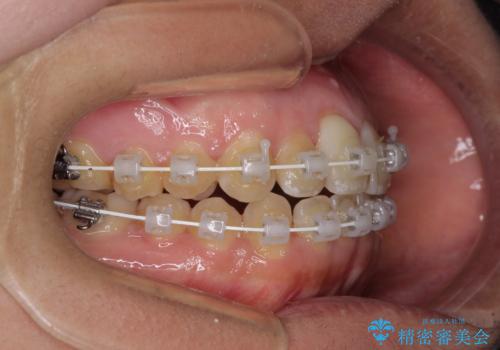

治療開始後すぐに妊娠され、つわりと闘いながらの矯正治療となりました。

上下顎でゴムかけを行ったのですが、早く終わらすためにしっかりと装着していただき、無事出産前に装置を外すことができました。